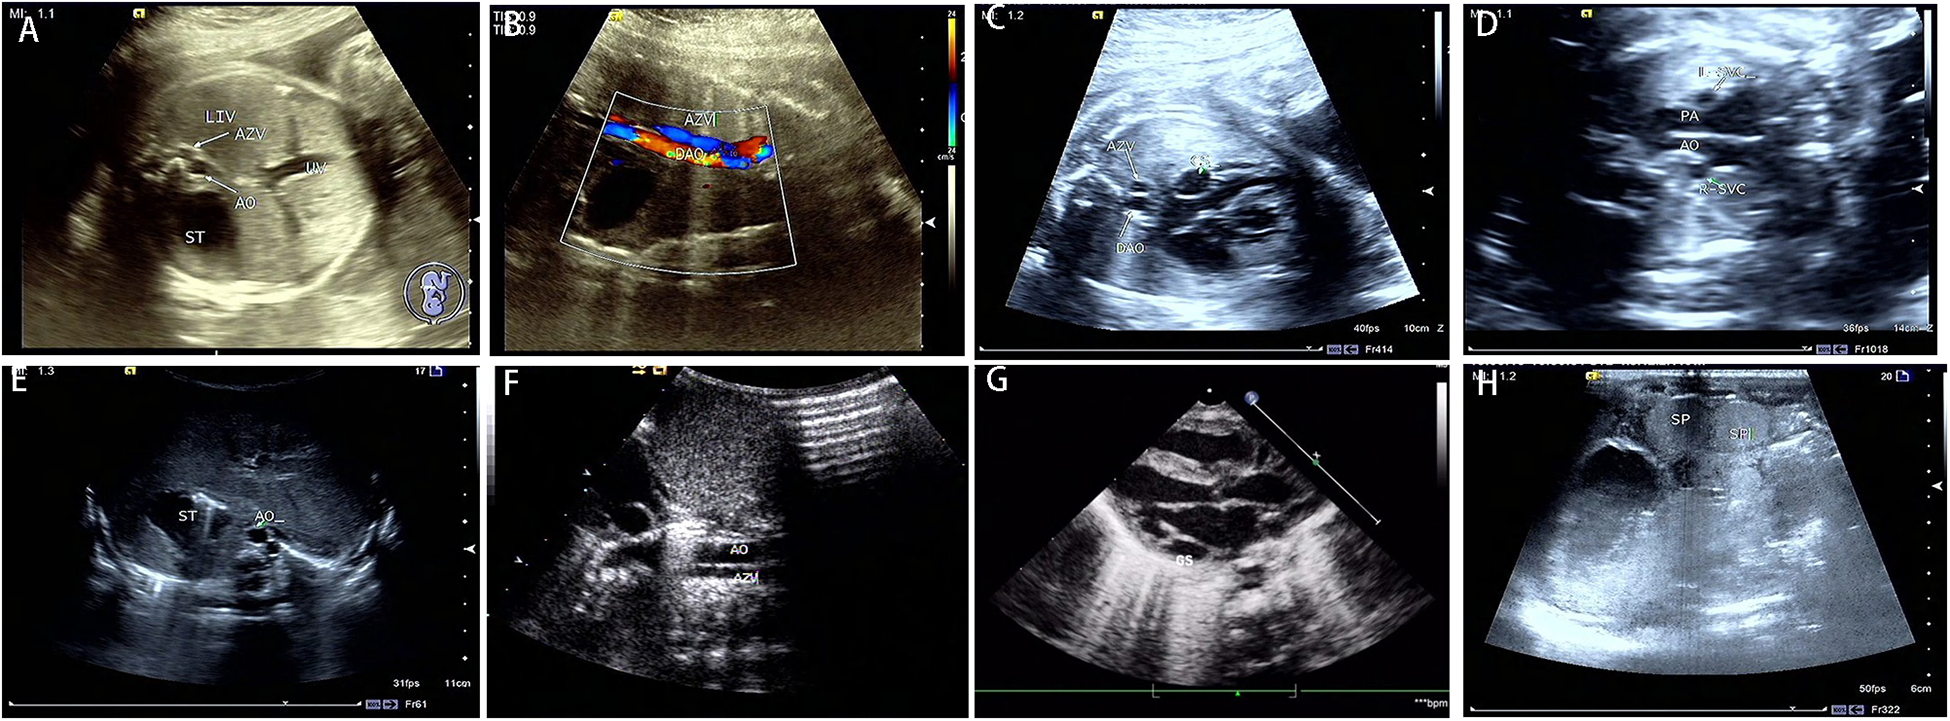

Figure 2

Prenatal and postnatal ultrasonography of LI fetuses. Prenatal sonography in the transverse section of the abdomen (A–D). (A) absence of a hepatic segment of IVC with dilated azygos; ST gastric vesicle, AO, abdominal aorta, AV azygos vein, and UV umbilical vein. (B) the parallel arrangement of the azygos vein and descending aorta. DAO, descending aorta. (C) the dilatation of coronary sinus. CS, coronary sinus. (D) double superior vena cava, L-SVC, left superior vena cava; R-SVC, right superior vena cava; PA, pulmonary artery. Postpartum sonograms (E–H): the images by postpartum sonography were consistent with prenatal ones.

The spectrum of cardiovascular and extracardiac lesions screened prenatally. Typical extracardiac malformations by ultrasonography in the 33 LI fetuses were as follows: gastric vesicles on different sides from the heart, absence of hepatic segment of the IVC, a parallel arrangement of the abdominal AO and the (semi) AV (Figures 2A,B), and double superior vena cava (Figure 2D). Further exploration of the venous drainage route in these LI fetuses revealed: hepatic veins infused separately with both atriums (6%); hepatic veins and ductus venous (DV) were separately introduced into both atriums (3%); or bilateral pulmonary veins flowed separately into both atriums (12%). Typical intracardiac malformations included atrioventricular septal defect, single atrium, left ventricular outflow tract obstruction, pulmonary atresia, double-outlet right ventricle, and bilateral left atrial appendage. Cardiac conduction abnormalities in the LI fetuses included sinus bradycardia and atrioventricular blockage. Other systemic abnormalities involved typical bilateral left bronchi, midline liver, and polysplenia. Atypical ultrasonographical signs detected included hypoplasia of the hepatic segment of the inferior vena cava with AV dilation, normal spleen morphology, and nondetectable atria and bronchi.